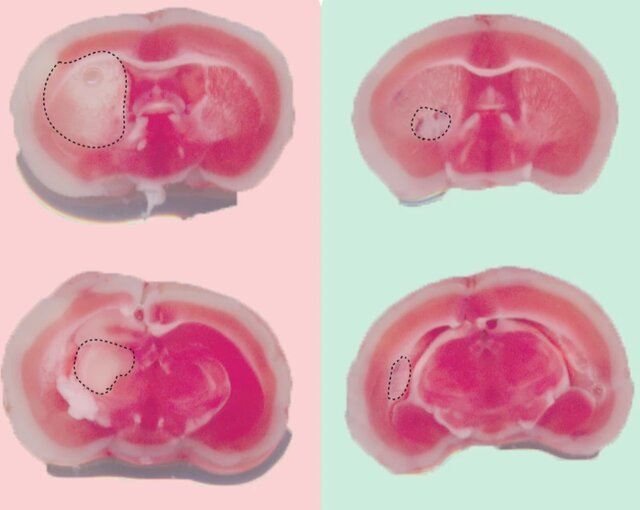

آزمایشها نشان داد که ناحیه آسیب دیده مغز موشهایی که TAT-DP-2 به آنها تزریق شده بود، پس از سکته، بسیار کوچکتر از موشهای درمان نشده است. عملکرد نورونها در موشهای درمان شده، بهتر و پایدارتر بود.